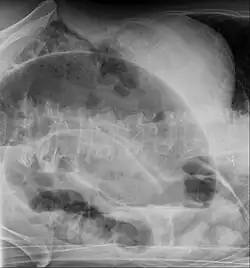

Coronal view of sigmoid volvulus with "whirlpool sign" -

After taking a thorough history, the diagnosis of colonic volvulus is usually easily included in the differential diagnosis. Abdominal plain x-rays are commonly confirmatory for a volvulus, especially if a coffee bean sign is seen. These refer to the shape of the air-filled closed loop of the colon, which forms the volvulus. Should the diagnosis be in doubt, a barium enema may demonstrate a "bird's beak" at the point where the segment of proximal bowel and distal bowel rotate to form the volvulus.

This area shows an acute and sharp tapering and looks like a bird's beak. If a perforation is suspected, barium should not be used due to its potentially lethal effects when distributed throughout the free intraperitoneal cavity. Gastrografin, which is safer, can be substituted for barium.